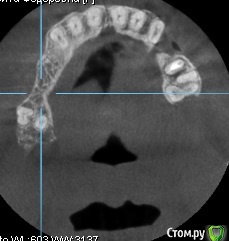

AAbdymomunov Опубликовано 24 июня, 2019 Поделиться Опубликовано 24 июня, 2019 Нужна помощь есть ли альтернатива вместо синуса? Пациент котегорически против синуса! 1 Ссылка на комментарий